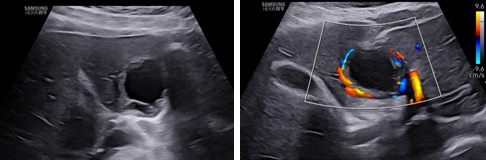

Hình 8, 9: Siêu âm lại sau 6 tuần trên thang xám và màu: khối thai viền mỏng dần với bờ không đều và những vùng hóa dịch trong thành.

Hình 10, 11: Siêu âm lại sau 12 tuần: lớp nguyên bào nuôi bong ra làm khối thai trở nên hỗn hợp hơn. Vẫn còn tín hiệu mạch máu quanh khối thai.

Bệnh nhân sau khi được chẩn đoán được theo dõi Beta HCG mỗi tuần, không có bất kì can thiệp ngoại khoa hay sử dụng Methotrexate. Sau 12 tuần, Beta HCG của bệnh nhân giảm còn 234 mUI/ml